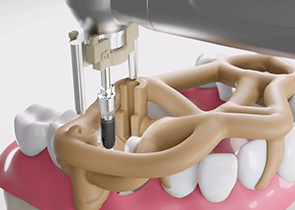

新一代口腔种植导板

西泰克双导(TwinGuide)数字化种植辅助系统,利用自研的TG-System系统、TG-Design设计软件、结合TG-Ai系统和设计团队为牙医提供安全可靠的种植方案,并通过3D打印生成产品。

双引导更精准

术野更开阔

冷却更充分

西泰克双导(TwinGuide)数字化种植辅助系统,利用自研的TG-System系统、TG-Design设计软件、结合TG-Ai系统和设计团队为牙医提供安全可靠的种植方案,并通过3D打印生成产品。